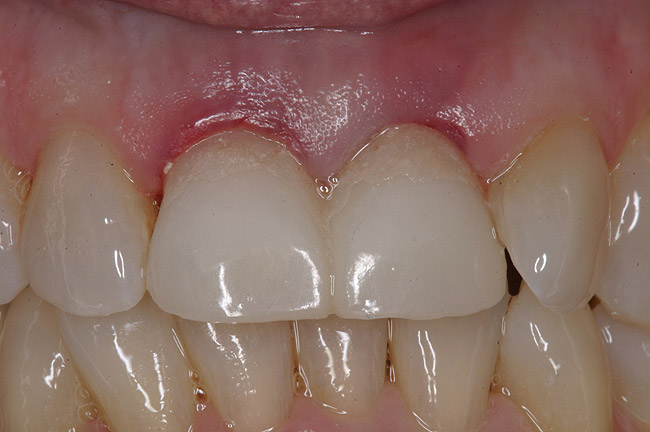

Figure 4  Final restoration of implants in the Nos. 8 and 9 sites 3 years after placement. Note the short central papilla regardless of the presence of bone. Restoration courtesy of Dr. Alan Goldberg.

Figure 4

Figure 5  A naturally low smile line hid the clinical “black triangle” from view.

Figure 5